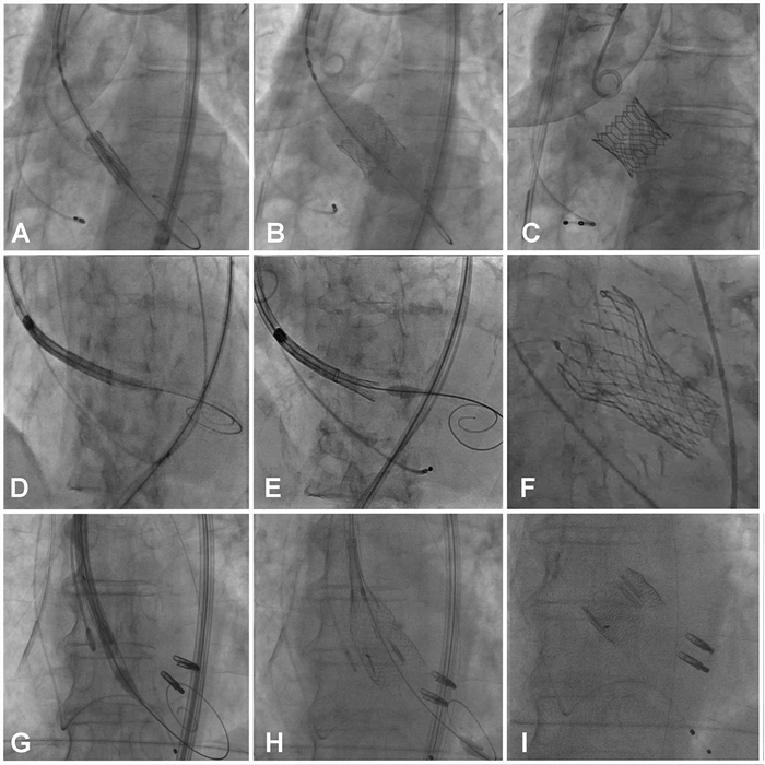

Figure 1. Technique to cross the aortic valve

The aortic valve is initially crossed with a soft-tipped straight wire (A, white arrow) with the aid of an Amplatz left 1 catheter (A). Once the valve is crossed (B), the wire is exchanged for a stiff wire with a curved tip (white arrow) to minimise ventricular injury (C) over which the TAVI device is then advanced.